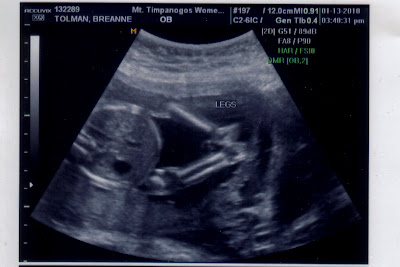

This is of it's face.

Did you see it??????

That's right!  We're having a GIRL!!!!!